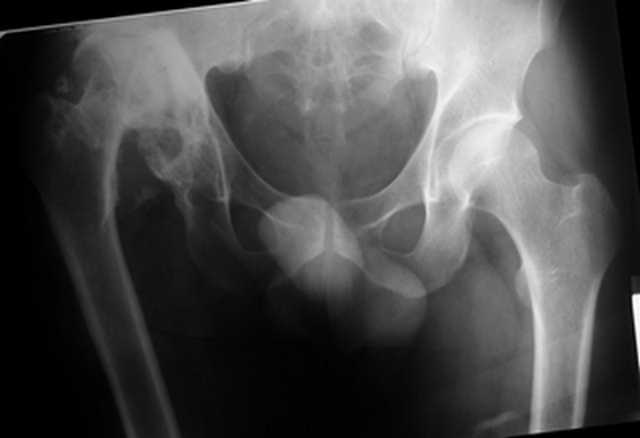

Уважаемые коллеги. Пациент 30 лет 3 года назад в результате травмы получил травматический дефект нижних конечностей до в/3 голеней, был пропущен вывих бедра.

В настоящее время очень неплохо ходит на протезах, движения в неоартрозе близки по объему к здоровой стороне. Основная жалоба - выраженная боль при ходьбе. планируем двухэтапное эндопротезирование - задним доступом мобилизовать проксимальный отдел бедра, резецировать шейку, аппаратом низвести бедро(головку оставить там где она есть, так как больших дефектов не видно(может пригодится в последующем?)). Вторым этапом бесцементное эндопротезирование. Насколько такой вариант реалистичен? Доступ для второго этапа? Может быть другие варианты?С уважением, Максим

Низводить надо обязательно, лучше в аппарате и лучше без остеотомии.

Если в аппарате низводиться не будет, то из небольшого доступа, лучше под контролем С-дуги выполнить остеотомию шейки. Без предварительного

низведения максимально возможная коррекция длины - 2,5-3 см.

Доступ - по предпочтениям хирурга, я предпочитаю передний с расширенной задней мобилизацией.

Решение по ВВ придется принимать по месту.... Сумеете "подрыться" и получить хорошее покрытие чашки (+2 винта об-но) - хорошо, если нет -

костная аутопластика из головки.